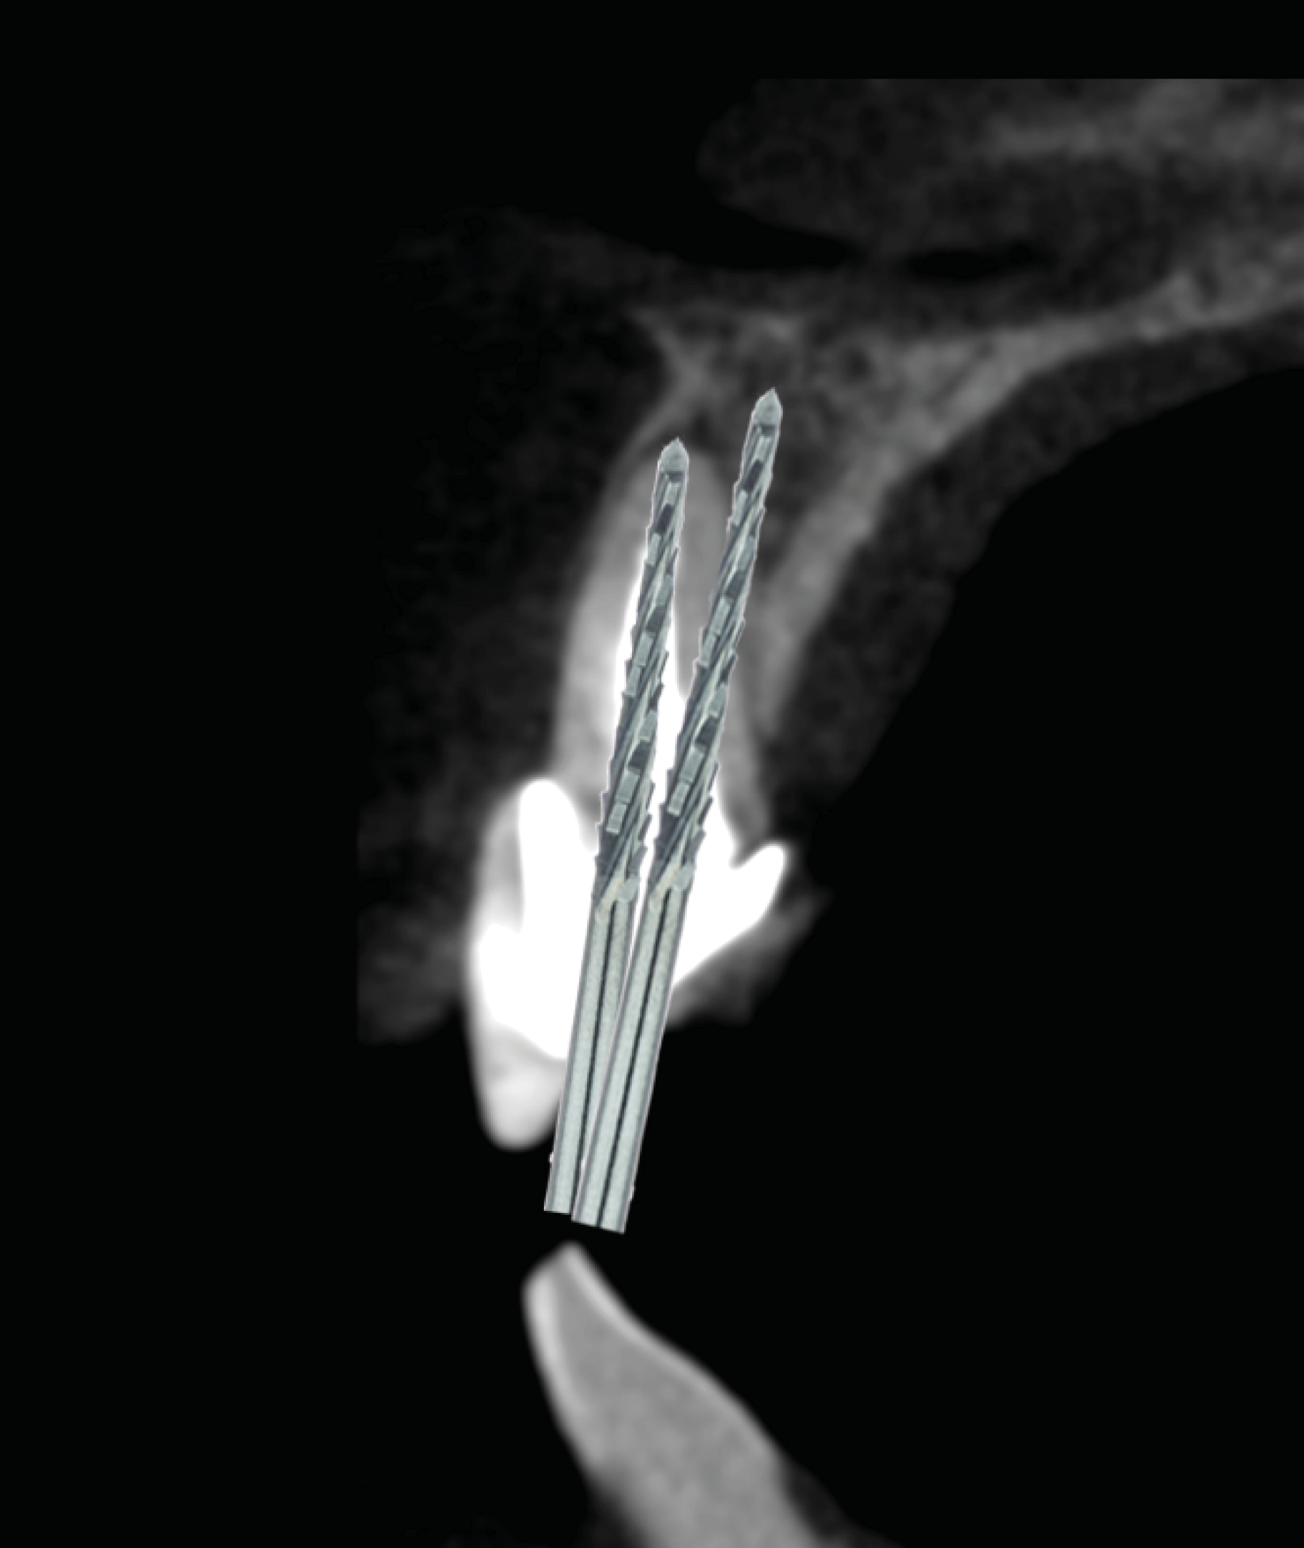

Fig 9. SPOT Step 4: Densah burs VT1525 (2.0) and VT1828 (2.3) are used at 1,200 rpm with irrigation in CW mode to widen the root canal hole trajectory to provide further and complete apex removal. The same burs are then used to establish the implant osteotomy. In some cases, the two trajectory holes might eventually overlap. (Figure 11 is a composite illustration provided by the authors.)

Figure 9

Fig 10. SPOT Step 4: Densah burs VT1525 (2.0) and VT1828 (2.3) are used at 1,200 rpm with irrigation in CW mode to widen the root canal hole trajectory to provide further and complete apex removal. The same burs are then used to establish the implant osteotomy. In some cases, the two trajectory holes might eventually overlap. (Figure 11 is a composite illustration provided by the authors.)

Figure 10

Fig 11. SPOT Step 4: Densah burs VT1525 (2.0) and VT1828 (2.3) are used at 1,200 rpm with irrigation in CW mode to widen the root canal hole trajectory to provide further and complete apex removal. The same burs are then used to establish the implant osteotomy. In some cases, the two trajectory holes might eventually overlap. (Figure 11 is a composite illustration provided by the authors.)

Figure 11